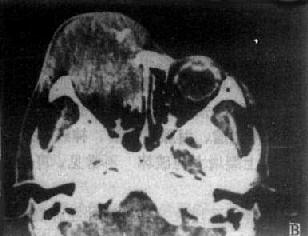

图5-2-2 眼眶CT扫描

左眼眶内炎性假瘤,弥漫性,眼正常结构消失,伴眼球突出

(二)眶内炎症(炎性假瘤) 这种非感染性炎症CT上有弥漫型和肿块型两种。前者CT可见眼环增厚,泪腺弥慢性增大,球后间隙密度增高,眼外肌肥大、密度增高,眶内各种结构分辨不清(图5-2-2B)可累及双眼。肿块型,除眼外肌与视神经增粗,眼环增厚外,还可见边缘清楚、密度均匀的块影。有时泪腺增大成一肿块。